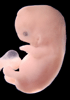

Carnegie Stage 19 (47 post-ovulatory days)

Most embryos at stage 19 are approximately 47-48 post-ovulatory days old and measure 17-20 mm in length. Distinguishing criteria for this stage include straightening of the trunk, the limbs extend nearly directly forward, toe rays are prominent, but interdigital notches have not yet appeared in the foot.

Although some of the photographs below show abnormal embryos, the animations and MRI slice images all depict normal embryos. Abnormal embryos are noted in the titles of the large photos when they are opened.